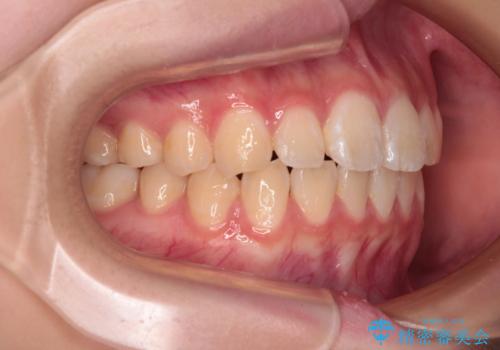

- 上下前歯のねじれを気にして来院された患者様です。

ワイヤー矯正でもマウスピース矯正でも対応可能でしたが、マウスピース矯正の自己管理が面倒であること、上顎前歯の捻転が著しいことから、ワイヤー矯正での治療を希望されました。

インビザライン治療が継続できない性別と年齢が世界的に調査されているそうですが、ほとんどの国で女子高生が最も多いとのことです。